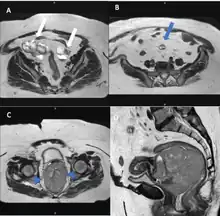

Magnetic resonance imaging

Although magnetic resonance (MRI) scans are not commonly employed for ovarian cancer detection, the majority of ultrasound-detected ovarian masses are usually benign. The combined approach of ultrasound with Doppler, along with the selective use of contrast-enhanced MRI, proves to be an efficient diagnostic method for identifying benign adnexal masses with distinctive features, including functional masses, dermoid, endometrioma, fibroma, pedunculated fibroid, hydrosalpinx, and peritoneal inclusion cysts.[19] This integrated diagnostic strategy is effective in preventing unnecessary surgical intervention. Additionally, the use of MRI contributes to a decrease in false-positive diagnoses, ultimately reducing the overall number of unnecessary surgical procedures related to ovarian masses.